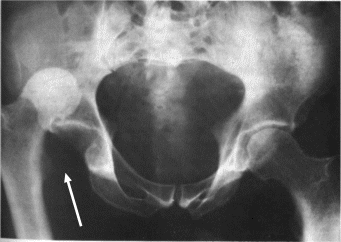

Hip Dislocation